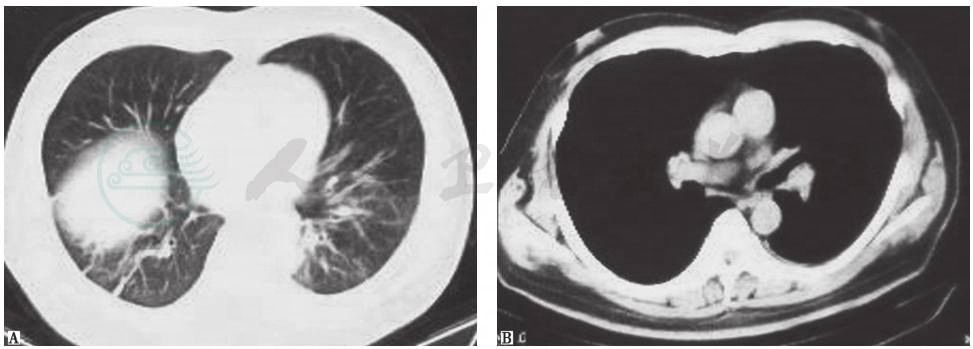

胸部CT、支气管动脉CT血管造影(CT angiography,CTA)和CTPA显示:①双肺动脉主干及分支多发栓塞(图2),右下肺渗出性实变(图3);②双侧支气管动脉未见扩张;③双侧少量胸腔积液。

图3 胸部CT表现(入院当天)

胸部CT可见右下肺渗出性实变病灶